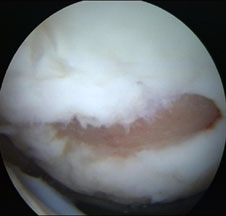

Chirurgul trebuie sa fie foarte atent atunci cand examineaza posteriorul condililor femurali. Daca se semnaleaza orice vatamare/rana/deteriorare pe suprafetele articulare, trebuie sa se cerceteze atent calitatea cartilagiului. Orice flapsuri instabile sunt inlaturate prin folosirea unui aparat de ras electric artroscopic sau curette. Apoi, un curette este folosit pentru a debrida stratul de cartilagiu calcifiat de la baza in toata grosimea defectului. Acest pas se bazeaza pe activitatea lui Frisbi, care a demonstrat vindecarea suprafetei articulare superioare la un cal, cand stratul cartilagiului calcifiat este indepartat. Cand indepartam stratul cartilagiului calcifiat, in general nu se foloseste un aparat de ras. Cu un aparat de ras este dificil de controlat cantitatea de os eliminat, si este posibil ca osul subcondral sa fie afectat.

Dupa indepartarea cu succes a stratului de cartilaj calcifiat, o andrea este folosita pentru a face mai multe gauri mici (mirofracturi) in osul expus al defectului condral aflate la distanta de 1-2 mm. Trebuie lasata o punte de oase potrivita intre gauri. Tehnica de microfracturi are numeroase avantaje fata de foraj. Mai intai de toate, creaza o leziune termala mai mica. Mai mult, cu microfracturi, chirurgul este capabil sa intre in zonele dificile ale suprafetei articulare cu un control mai bun asupra adancimii de patrundere. La finalizarea microfracturii, o suprafata aspra este generata pentru a aderenta cheagului de sange care contine celule mezenchimale nediferentiate de la osul subcondral. Trebuie avut grija ca cele mai marginase parti ale leziuni sa fie patrunse de andrea pentru a ajuta la vindecarea tesutului reparator la imprejmuirea suprafetei articulare. Odata ce microfractura este finalizata, pompa artroscopica este oprita pentru a se asigura ca sangerarea maduvei curge din gaurile mici umpland defectul.[54]

Artroscopia arata repararea tesuturilor la sase saptamani.